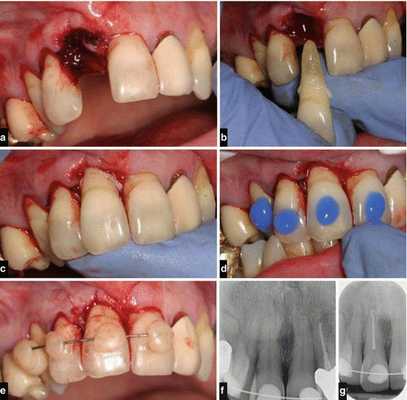

Лечение полного вывиха

В случае полного вывиха зуба, если с момента травмы прошло не более двух суток, проводится его реплантация (установка зуба обратно в лунку) [8] .

Реплантацию проводят по общепринятой методике:

- Травмированный зуб промывают и помещают в изотонический раствор натрия хлорида с антибиотиками до самой операции.

- Если после вывиха прошло не более 10 часов, можно реплантировать зуб, не проводя эндодонтическое лечение (лечение корневых каналов). В таком случае эндодонтическое лечение зуба проводят через 2-3 недели после реплантации, когда становится очевидным приживление зуба.

- Если с момента вывиха прошло более 10 часов, пульпу полностью удаляют, а канал после механической и медикаментозной обработки пломбируют. Зуб после реплантации выводят из прикуса и укрепляют путём шинирования с помощью пластмассовой шины-каппы. Снимают её только через 3-4 недели.

- После реплантации необходимо в течение от одного до двенадцати месяцев проводить рентгенологический контроль. Это позволяет судить о состоянии корня зуба, периодонта и кости.

Необходимо отметить, что самые благоприятные результаты получены при проведении реплантации через 20-30 минут после вывиха.